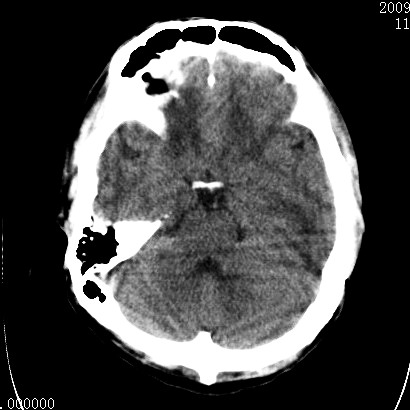

以下是引用余辉在2009-4-9 17:34:00的发言:[br]双侧脑白质对称性弥漫性密度减低,脑室脑沟裂池变小,双侧豆状核对称低密度,脑干对称性低密度,考虑1中毒性脑病2电解质异常(低钾钠等)3代谢异常及维缺乏等,进一步检查。